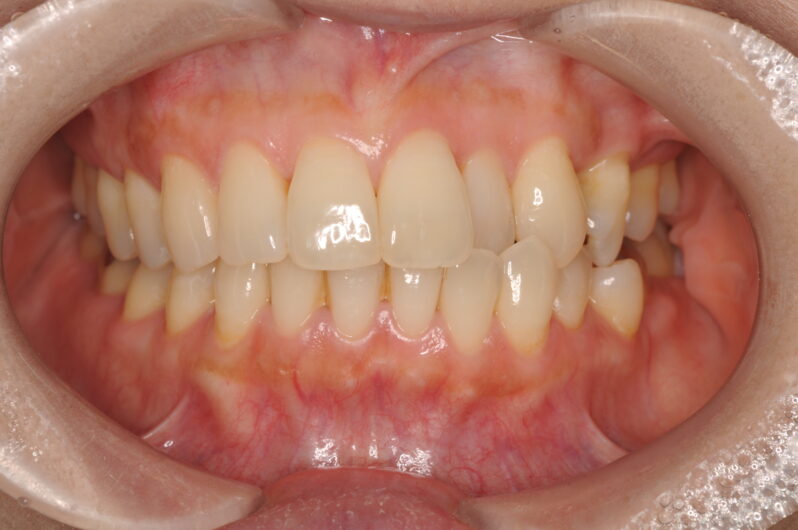

こちらが、初診時のAさんのレントゲンと写真です。

一見すると、大きな問題はないように見えるかもしれません。しかし、専門的な視点から分析すると、いくつかの重要な問題点が浮かび上がってきました。

最大の原因は、左上の前から2番目の歯(専門用語で「側切歯」)が、下の歯に強く引っかかり、顎がスムーズに動くのを妨げていたことです。毎日、食事や会話のたびに、この「引っかかり」が顎の関節や周りの筋肉に不自然な力を加え続けていました。これが、慢性的な頭痛や耳鳴りの引き金となっていたのです。

さらに、以前に左上の奥歯(5番目の歯)を抜いたままにしていたことで、歯並び全体が少しずつ変化し、かみ合わせのずれをさらに悪化させている状態でした。